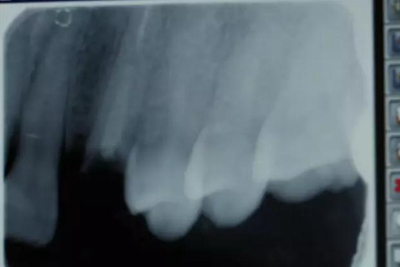

患者女性,55歲,3年前B3纖維樁+鑄瓷全冠修復(fù),一周前牙冠折斷,就診后,發(fā)現(xiàn)纖維樁根管口處折斷,周圍牙齦增生,建議患者行冠延長(zhǎng)手術(shù)。首先去除斷端的纖維樁。拍片示牙根長(zhǎng)度充足。于是開始冠延長(zhǎng)手術(shù)。

因?yàn)槭乔把?,故該患者將?lái)修復(fù)體邊緣必須為齦下,所以3個(gè)月后再行修復(fù)。以下為手術(shù)前照片。